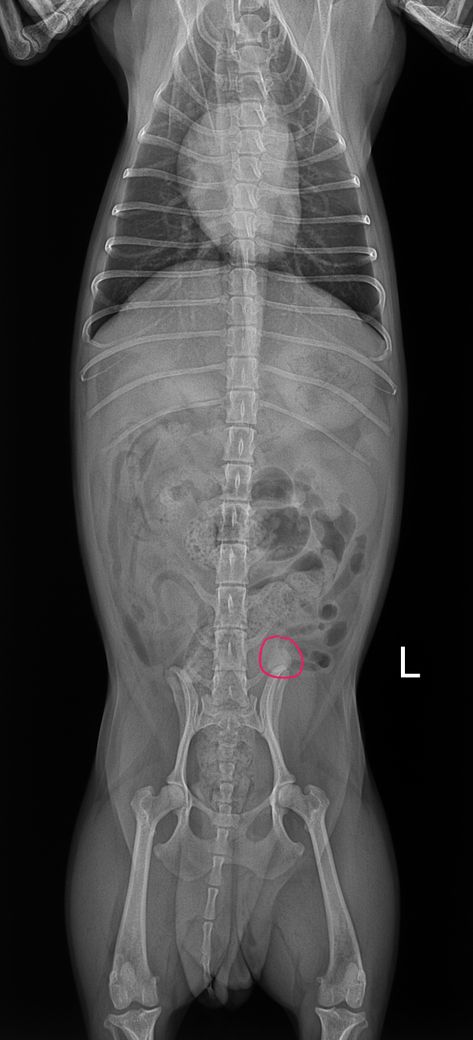

8살 암컷 강아지이고 어제 유선종양이랑 중성화 수술했는데 수술 전에 찍은 엑스레이에서 궁금한 점이 생겨 물어봅니다 혹시 엑스레이 상에서 제가 빨간색으로 동그라미 친 부분이 뭔 지 알 수 있을까요? 정확하게능 아니더라도 가늠이라던지 한번만 봐주세요..

복배상에서는 무기질 밀도로 보이지만 외측사에서는 동일한 밀도의 구조체가 보이지 않고, 해당 위치 수준으로 유두 즉, 젖꼭지가 외측상에서 대형으로 관찰되어 젖꼭지가 복배상에서 겹쳐 강조된 상태로 보입니다.

즉, 젖꼭지입니다.

• 외측상에서는 대변 때문에 가려져서 잘 보이지 않지만, 복배상에서는 원형으로 보이는듯 합니다.

일차적으로 배속에 있는 대변이 어느정도 다 빠진 후 다신 방사선 촬영하시는 것을 권유드립니다.